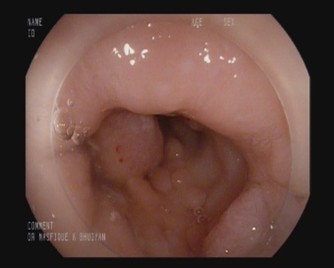

Refer to caption

Figure 1: Examples of colorectal polyp morphologies observed during colonoscopy. (a) Sessile polyp lying flat against the colonic mucosa, making detection more challenging.(b, c) Pedunculated polyps with stalk-like structures protruding from the mucosal surface.

Colorectal polyps generally exhibit two distinct morphologies: sessile (flat) and pedunculated (stalked) as shown in Fig.1. Sessile polyps, which are now recognized as more prevalent than once believed, are particularly challenging to detect during colorectal cancer screening due to their flat structure that closely adheres to the mucosal surface of the colon. In contrast, pedunculated polyps resemble a mushroom-like structure, protruding from the mucosal lining and connected by a narrow, elongated stalk [13] .